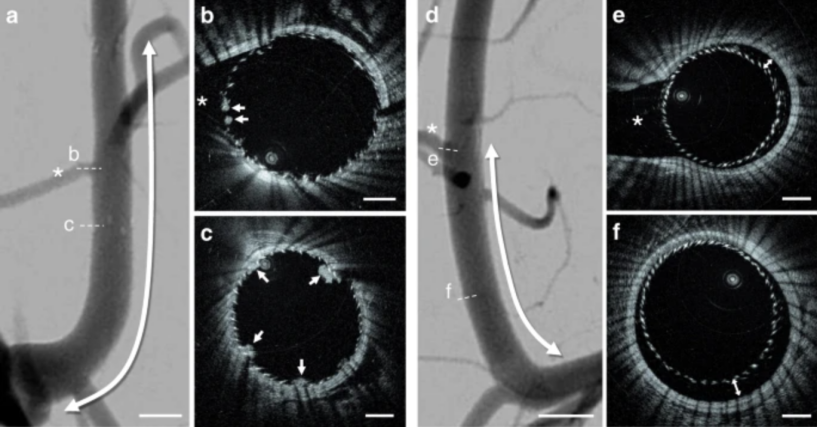

另一类则是将(高频)OCT技术嫁接到神经血管,进行成像分析,与冠脉的技术逻辑类似。尽管目前还只是一些尝试,但对于未来治疗卒中病患来说,则是多了一种好助手。